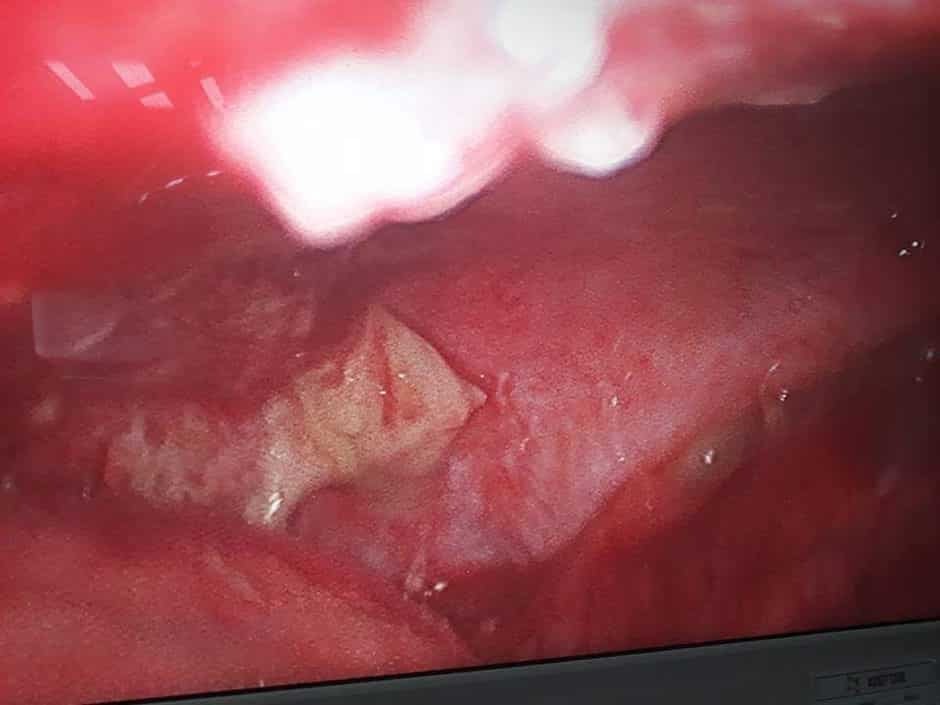

A Young lady who was a small kid...when her mother was operated for a Complex Gastrointestinal condition almost 14 years back by Dr Suddhasattwa Sen suddenly came in with severe blood loss from Gastrointestinal tract with a loss of almost 2 to 3 litres of blood with Shock with fainting . Further stabilisation was done and then extensive investigation revealed not only Piles and GI Ulcers but also SRUS Bleeding ulcers in rectum. A condition called Solitary Rectal Ulcer Syndrome ( a complex and difficult to cure anorectal problem ) . Her hemoglobin dropped to below 7 gm% She finally underwent surgery after 5 days and left home after 2 days post op without any further bleed or problems .